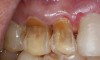

If a patient has risk factors that can contribute to dental erosion, an examination will reveal clinical signs and symptoms of dental erosion. It is unlikely that dental erosion will be seen without other contributing factors. Tooth wear and abrasion typically occur in combination with dental erosion. In the clinical evaluation of tooth surfaces for the diagnosis of erosion, what is typically seen are smooth, shiny surfaces of the teeth where the usual anatomic form of the tooth should be. In patients ingesting very acidic diets, the facial surfaces of anterior teeth are very smooth, and if the beverages being ingested have high sugar content, these teeth may have caries at their facial gingival margins (Figure 1). The occlusal surfaces of posterior teeth in the more advanced stages of erosion due to regurgitation may have extensive exposed dentinal areas with loss of anatomic form (Figure 2). In some cases, the chemical erosion combined with toothbrush–toothpaste abrasion can remove all the enamel, leaving only the dentin exposed (Figure 3). These teeth may exhibit sensitivity. Posterior teeth with restorations may demonstrate fillings that are higher than the surrounding occlusal surfaces of the enamel. Anterior teeth may demonstrate more incisal translucency due to tooth loss at the incisal edge. In patients with the eating disorder bulimia nervosa, who vomit, the hydrochloric acid causes extensive damage to the lingual surfaces of the anterior teeth, where the enamel is lost, leaving exposed dentin (Figure 4).

Figure 3  In a patient who smoked a pipe, the nicotinic acid causing tooth erosion was accentuated by the use of a highly abrasive smoker’s toothpaste. Some of the teeth have been restored with bonded composite resin.

Figure 3